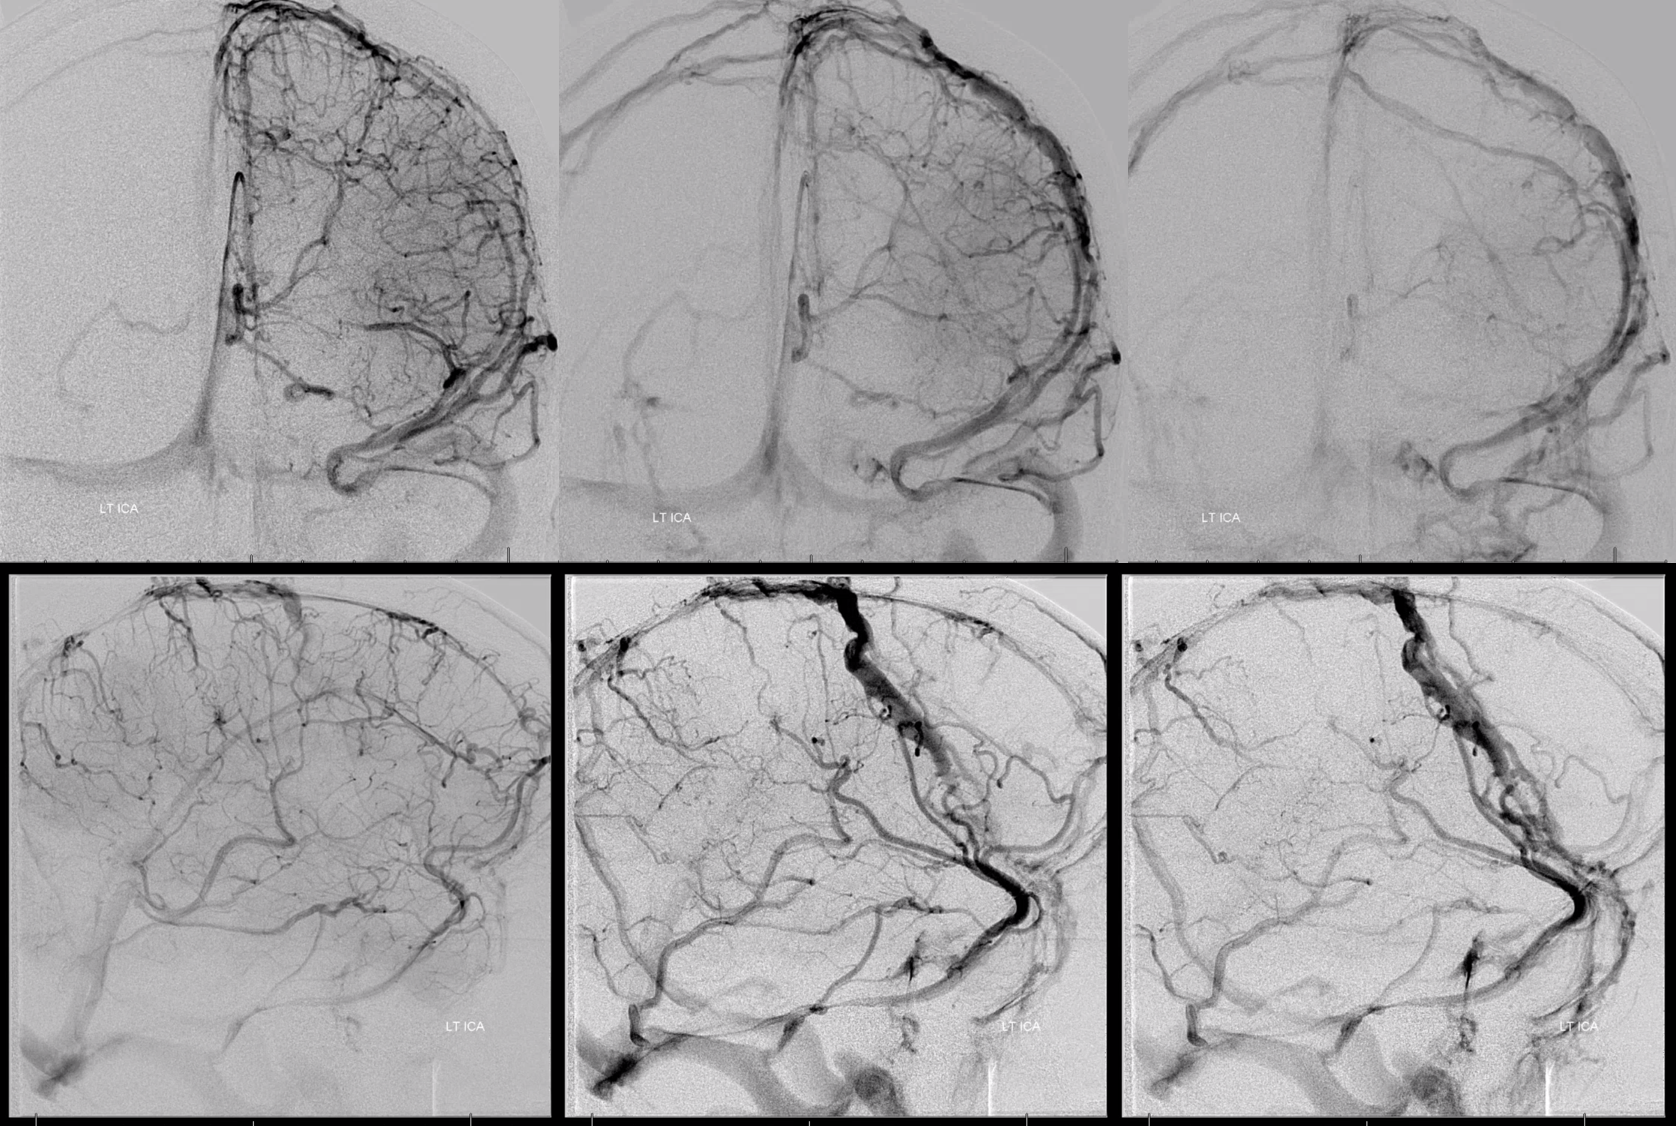

All of the above anatomic knowledge can become very useful in evaluation of venous thrombosis. Numerous collateral pathways develop in this setting attempting to compensate for the loss. The most dramatic cases usually involve the largest channel — the superior sagittal sinus. In this case, a man presented with what initially was thought to be vasculitis-related brain hemorrhage. Subsequent workup led to an angiogram, where sagittal sinus thrombosis with extensive trans-cerebral and trans-osseous emissary vein collateral channels was seen. In retrospect, these findings were present on the patient’s earlier contrast MRI. “Venovibe” or other contrast-enhanced MR venograms can very sensitive, particularly when interpreted with the appropriate index of suspicion. Noncontrast 2-D time of flight MRV I consider to be next to useless as a problem-solving technique. Any thin-slice postcontrast T1 study is vastly superior.